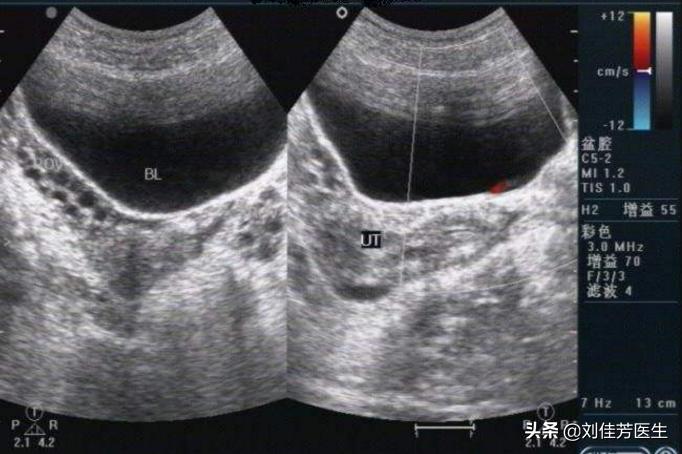

- 10.单侧,月经周期长短交替出现,阴道B超发现一侧卵巢多囊改变另一侧正常。